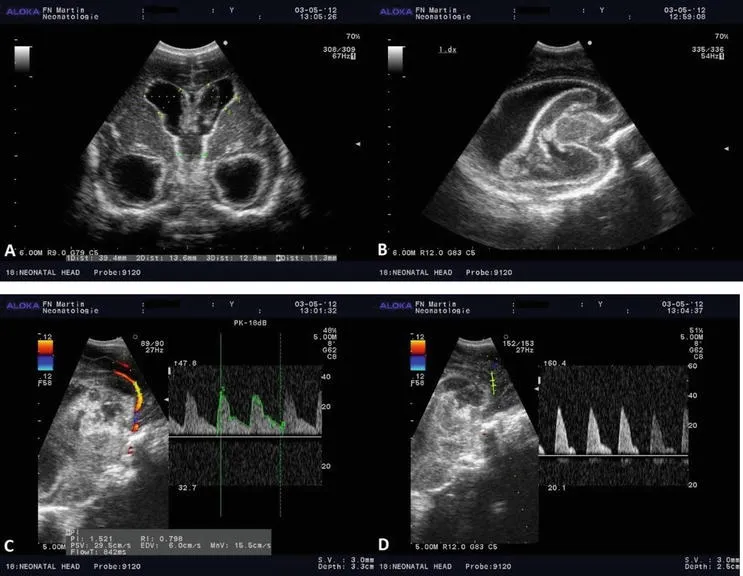

ಬೆಂಗಳೂರು: ಪ್ರತಿಷ್ಠಿತ ಮಲ್ಟಿ ಸ್ಪೆಷಾಲಿಟಿ ಆಸ್ಪತ್ರೆಯಾದ ಬನ್ನೇರುಘಟ್ಟ ರಸ್ತೆಯ ಅಪೋಲೋ ಆಸ್ಪತ್ರೆಯು, 1,000 ಟ್ರಾನ್ಸ್‌ ಕ್ರೇನಿಯಲ್ ಡಾಪ್ಲರ್ (ಟಿಸಿಡಿ) ಪ್ರಕ್ರಿಯೆಗಳನ್ನು ಯಶಸ್ವಿಯಾಗಿ ಪೂರ್ಣಗೊಳಿಸಿ ಮಹತ್ವದ ಸಾಧನೆ ಮಾಡಿದೆ. ಪಾರ್ಶ್ವವಾಯು ರೋಗನಿರ್ಣಯ ಮತ್ತು ನ್ಯೂರೋ ಕ್ರಿಟಿಕಲ್ ಕೇರ್ ಮೇಲ್ವಿಚಾರಣೆಯಲ್ಲಿ ಈ ತಂತ್ರಜ್ಞಾನವು ಅತ್ಯಂತ ಪರಿಣಾಮಕಾರಿಯಾಗಿದ್ದು, ಆಸ್ಪತ್ರೆಯ ಈ ಸಾಧನೆಯು ವೈದ್ಯಕೀಯ ಕ್ಷೇತ್ರದಲ್ಲಿ ಮಹತ್ವದ ಮೈಲಿಗಲ್ಲಾಗಿದೆ.

ಈ 1,000 ಪ್ರಕ್ರಿಯೆಗಳ ಅವಧಿಯಲ್ಲಿ, ಟಿಸಿಡಿ ತಂತ್ರಜ್ಞಾನವು ಆಸ್ಪತ್ರೆಯಲ್ಲಿ ಸಾಮಾನ್ಯ ಮತ್ತು ಸುಧಾರಿತ ಪಾರ್ಶ್ವವಾಯು ಮೌಲ್ಯಮಾಪನ ಮಾಡಲು ಅನುವು ಮಾಡಿಕೊಟ್ಟಿದೆ. ಇದರಲ್ಲಿ ತೀವ್ರ ಪಾರ್ಶ್ವವಾಯುವಿಗೆ ಒಳಗಾದ 350ಕ್ಕೂ ಹೆಚ್ಚು ರೋಗಿಗಳ ಮೇಲ್ವಿಚಾರಣೆಯನ್ನೂ ಮಾಡಲಾಗಿದೆ. ಈ ತಂತ್ರಜ್ಞಾನವು ಮೆದುಳಿನ ಒಳಗಿನ ರಕ್ತನಾಳಗಳ ಸಂಕುಚಿತಗೊಳ್ಳುವಿಕೆ, ಅಡೆತಡೆಗಳು ಮತ್ತು ರಕ್ತಪರಿಚಲನೆಯ ಅಸಮಾನತೆಯನ್ನು ತ್ವರಿತವಾಗಿ ಗುರುತಿಸಲು ಸಹಾಯ ಮಾಡಿದೆ.

ಇದು ವೈದ್ಯರಿಗೆ ಸಮಯೋಚಿತ ಚಿಕಿತ್ಸಾ ನಿರ್ಧಾರಗಳನ್ನು ತೆಗೆದುಕೊಳ್ಳಲು ಮತ್ತು ದ್ವಿತೀಯ ಪಾರ್ಶ್ವವಾಯು ತಡೆಗಟ್ಟುವಿಕೆಗೆ ಮಾರ್ಗದರ್ಶನ ನೀಡಲು ನೆರವಾಗಿದೆ. ಅಲ್ಲದೆ, ಇದು 'ಮೊಯ ಮೊಯಾ' ಕಾಯಿಲೆಯಲ್ಲಿ ಪರ್ಯಾಯ ರಕ್ತಪರಿಚಲನೆಯನ್ನು ಪತ್ತೆಹಚ್ಚಲು ಮತ್ತು ಸಬ್‌ ಕ್ಲೇವಿಯನ್ ಸ್ಟೀಲ್ ಫಿನಾಮಿನನ್ ನಂತಹ ನಾಳಗಳ ಪರಿಸ್ಥಿತಿಗಳ ಕುರಿತು ರೋಗನಿರ್ಣಯ ಮಾಡಲು ನೆರವು ನೀಡಿದೆ.

ಈ ಸಾಧನೆಯ ಪ್ರಾಮುಖ್ಯತೆಯ ಬಗ್ಗೆ ಮಾತನಾಡಿದ ಬನ್ನೇರುಘಟ್ಟದ ಅಪೋಲೋ ಆಸ್ಪತ್ರೆಯ ಕನ್ಸಲ್ಟೆಂಟ್ ನ್ಯೂರಾಲಜಿಸ್ಟ್ ಡಾ. (ಪ್ರೊ.) ಸೂರ್ಯನಾರಾಯಣ ಶರ್ಮ ಪಿ.ಎಂ. ಅವರು, "ಟಿಸಿಡಿಯನ್ನು ಅಕ್ಷರಶಃ ನರರೋಗ ತಜ್ಞರ 'ಮೆದುಳಿನ ಸ್ಟೆಥಾಸ್ಕೋಪ್' ಎಂದು ಕರೆಯ ಲಾಗುತ್ತದೆ. ಏಕೆಂದರೆ ಇದು ರೋಗಿಯ ಹಾಸಿಗೆಯ ಬಳಿಯೇ ಮೆದುಳಿನ ರಕ್ತಪರಿಚಲನೆಯನ್ನು ನೈಜ ಸಮಯದಲ್ಲಿ ಮೌಲ್ಯಮಾಪನ ಮಾಡಲು ನಮಗೆ ಅವಕಾಶ ನೀಡುತ್ತದೆ.

ಸಾಂಪ್ರದಾಯಿಕ ಇಮೇಜಿಂಗ್‌ ಗಿಂತ ಭಿನ್ನವಾಗಿ, ಇದು ಮೆದುಳಿನ ಧಮನಿಗಳ ಮೂಲಕ ರಕ್ತವು ನಿಜವಾಗಿ ಹೇಗೆ ಹರಿಯುತ್ತಿದೆ ಎಂಬ ಒಳನೋಟವನ್ನು ನೀಡುತ್ತದೆ. ಇದು ಪಾರ್ಶ್ವವಾಯು ಮೌಲ್ಯಮಾಪನ ಮತ್ತು ನ್ಯೂರೋಕ್ರಿಟಿಕಲ್ ಕೇರ್ ಮೇಲ್ವಿಚಾರಣೆಯಲ್ಲಿ ನಿರ್ಣಾಯಕ ಪಾತ್ರ ವಹಿಸುತ್ತದೆ. 1,000 ಪ್ರಕ್ರಿಯೆಗಳ ಈ ಮೈಲಿಗಲ್ಲನ್ನು ತಲುಪಿರುವುದು, ನಮ್ಮ ಸಮಗ್ರ ಪಾರ್ಶ್ವ ವಾಯು ಚಿಕಿತ್ಸೆಯಲ್ಲಿ ಈ ತಂತ್ರಜ್ಞಾನವು ಹೇಗೆ ಅತ್ಯಗತ್ಯ ಭಾಗವಾಗಿದೆ ಎಂಬುದನ್ನು ಸಾರುತ್ತದೆ ಮತ್ತು ರೋಗಿಗಳಿಗೆ ವೇಗವಾಗಿ ಹಾಗೂ ಹೆಚ್ಚು ನಿಖರವಾದ ಚಿಕಿತ್ಸಾ ನಿರ್ಧಾರಗಳನ್ನು ತೆಗೆದು ಕೊಳ್ಳಲು ನಮಗೆ ಸಹಾಯ ಮಾಡುತ್ತದೆ," ಎಂದು ತಿಳಿಸಿದರು.